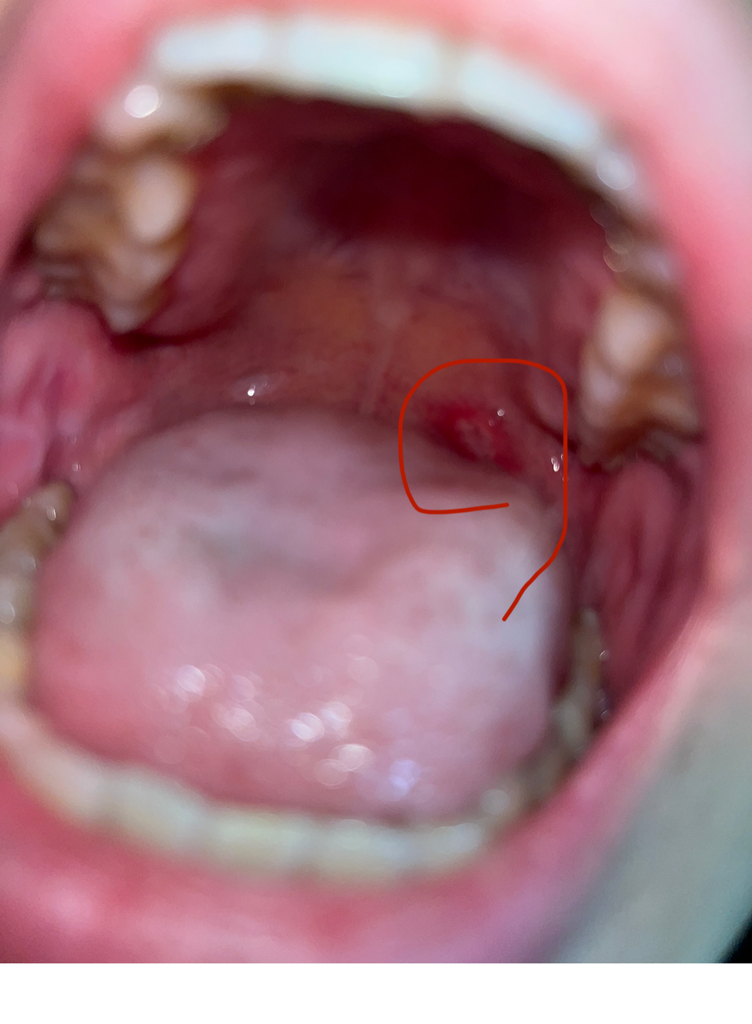

구내염이 점점 커지고 낫지를 않습니다.

한 일주일 전쯤 구내염이 안쪽에 낫는데요. 점점 커지면서 낫지를 않습니다.

이비인후과 방문후 가글 및 진통제를 받아서 먹고있구요, 페리덱스랑 뿌리는 약도 바르고 있는데 점점 커집니다.

구강 내과를 방문해야할까요? 시간이 지나면 자연스레 없어질지, 어떻게 치료하면 좋을지 문의드립니다.

• 1번 째 사진